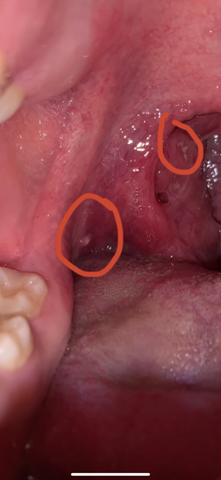

Weisser Pickel Im Mund Rachenraum Gesundheit Und Medizin Zahnarzt Entzundung

Flecken Im Rachen Noch Mal Mit Bild Pickel

Pickel im Rachen, sind in der Regel ein Zeichen der Irritation Ihr äußeres Erscheinungsbild, einschließlich der Farbe, hilft deinem Arzt, die zugrunde liegende Ursache zu erkennen Viele Ursachen sind nicht schwerwiegend, aber einige erfordern einen umgehenden Besuch bei deinem Arzt.

Eiterpickel im Rachen weisen die gleichen Eigenschaften auf wie Pickel an anderen Körperstellen Im Rachen können sie sehr schmerzhaft sein, die die Lebensqualität des Betroffenen einschränken, weil zum Beispiel Sprechen und Schlucken erschwert sind Mögliche Ursachen sind Reizung durch Allergie oder ein geschwächtes Immunsystem sowie kleine Verletzungen der Schleimhaut. Mechanische Irritationen, also Druckstellen im Mund und an der Zunge, etwa durch Aphthen rufen teils intensive Schmerzen im Mund hervor Sie erscheinen als milchigweiße belegte Flecken, häufig mit einer umgebenden Rötung Aphthen sind kleine, überaus schmerzhafte Schleimhautschäden, die meist in Form von Bläschen im Mund auftreten. Es war ein Pickel im Gesicht und passiert nicht oder findet.

Pickel im Rachen gibt es so gar nicht Entweder du hast eine Hals oder Mandelentzündung und es haben sich winzige EiterAnsammlungen gebildet Eine zweite Möglichkeit sind Aphten Dabei handelt es sich um harmlose punktuelle Entzündungen der Mundschleimhaut, die sich natürlich auch im Rachen und anderen Stellen in der Mundhöhle ansetzen. Hallo ich hab eine weiße Stelle im Mund (siehe Bild) und neben dran überall kleine rote punkte, es sieht aus wie getrocknetes Blut aber es geht auch nicht weg Weiß einer was das ist?. Wenn Sie eines dieser Symptome bemerken und weiße Flecken auf Ihrem Zahnfleisch bemerken, sehen Sie sofort Ihren Zahnarzt Wenn Sie weiße Flecken auf dem Zahnfleisch mit neuen Symptomen wie Schmerzen, einem Baumwollgefühl im Mund und Blutungen haben, die sich nicht innerhalb einer Woche auflösen, vereinbaren Sie einen Termin mit Ihrem Zahnarzt.

Mandelsteine (Tonsillensteine) sind weißgelbliche Gebilde, die aus verschiedenen Substanzen in den Gaumenmandeln entstehen Sie sind wenige Millimeter groß, von meist fester oder krümeliger Konsistenz und können Mundgeruch verursachen Ansonsten sind Mandelsteine harmlos, nur selten führen größere Exemplare zu weiteren Beschwerden. Weiße Punkte im Rachen müssen nicht sofort darauf schließen, dass Sie schwer krank sind Um gottes Willen bitte machen Sie sich nicht direkt solche Sorgen Die weißen Punkte sind nahezu 80 Prozent ein Zeichen dafür, dass Sie entweder krank werden oder bereits erkältet sind. In vielen Fällen waren die Materialien verschmutzt oder die Rasiertechnik ist verbesserungswürdig Talgdrüsenhyperplasie Vor allem Frauen mit fettiger oder Mischhaut entdecken ab 40 Jahren auf einmal kleine, hartnäckige Knötchen mit einer hellen Umrandung im Gesicht Hautschädigungen, die zu einer.

Die Patientin ist verzweifelt – das sei nun schon das dritte „Bläschen im Mund“ innerhalb von nur einer Woche So langsam reiche es ihr, sie könne weder normal essen noch trinken. Im Laufe der Zeit werden sie aber von selbst von den Gaumenmandeln freigegeben Es ist auch manchmal möglich, kleinere Steine durch Schlucken bei geschlossenem Mund selbst herauszusaugen Es ist ebenfalls möglich, eine Munddusche zu verwenden, um die Mandelgrüfte zu reinigen und die weitere Entstehung von Tonsillensteinen zu verhindern. Pickel im Rachen gibt es so gar nicht Entweder du hast eine Hals oder Mandelentzündung und es haben sich winzige EiterAnsammlungen gebildet Eine zweite Möglichkeit sind Aphten Dabei handelt es sich um harmlose punktuelle Entzündungen der Mundschleimhaut, die sich natürlich auch im Rachen und anderen Stellen in der Mundhöhle ansetzen.